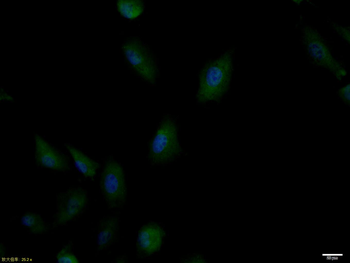

应用稀释比例:IHC-P=1:100-500, IHC-F=1:100-500, ICC/IF=1:100-500, IF=1:100-500, Flow-Cyt=1μg /test